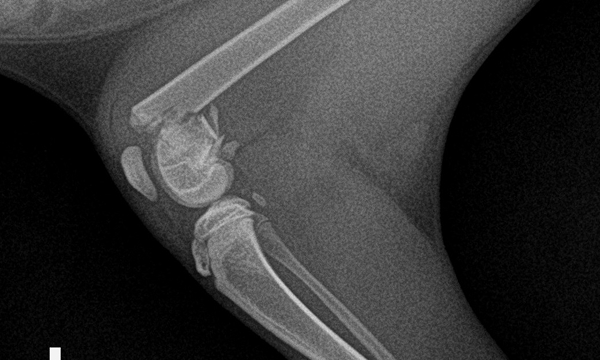

수술케이스 ③ 배*강아지 - 대퇴골 분쇄골절

수술케이스 3 before BEFORE

수술케이스 3 after AFTER